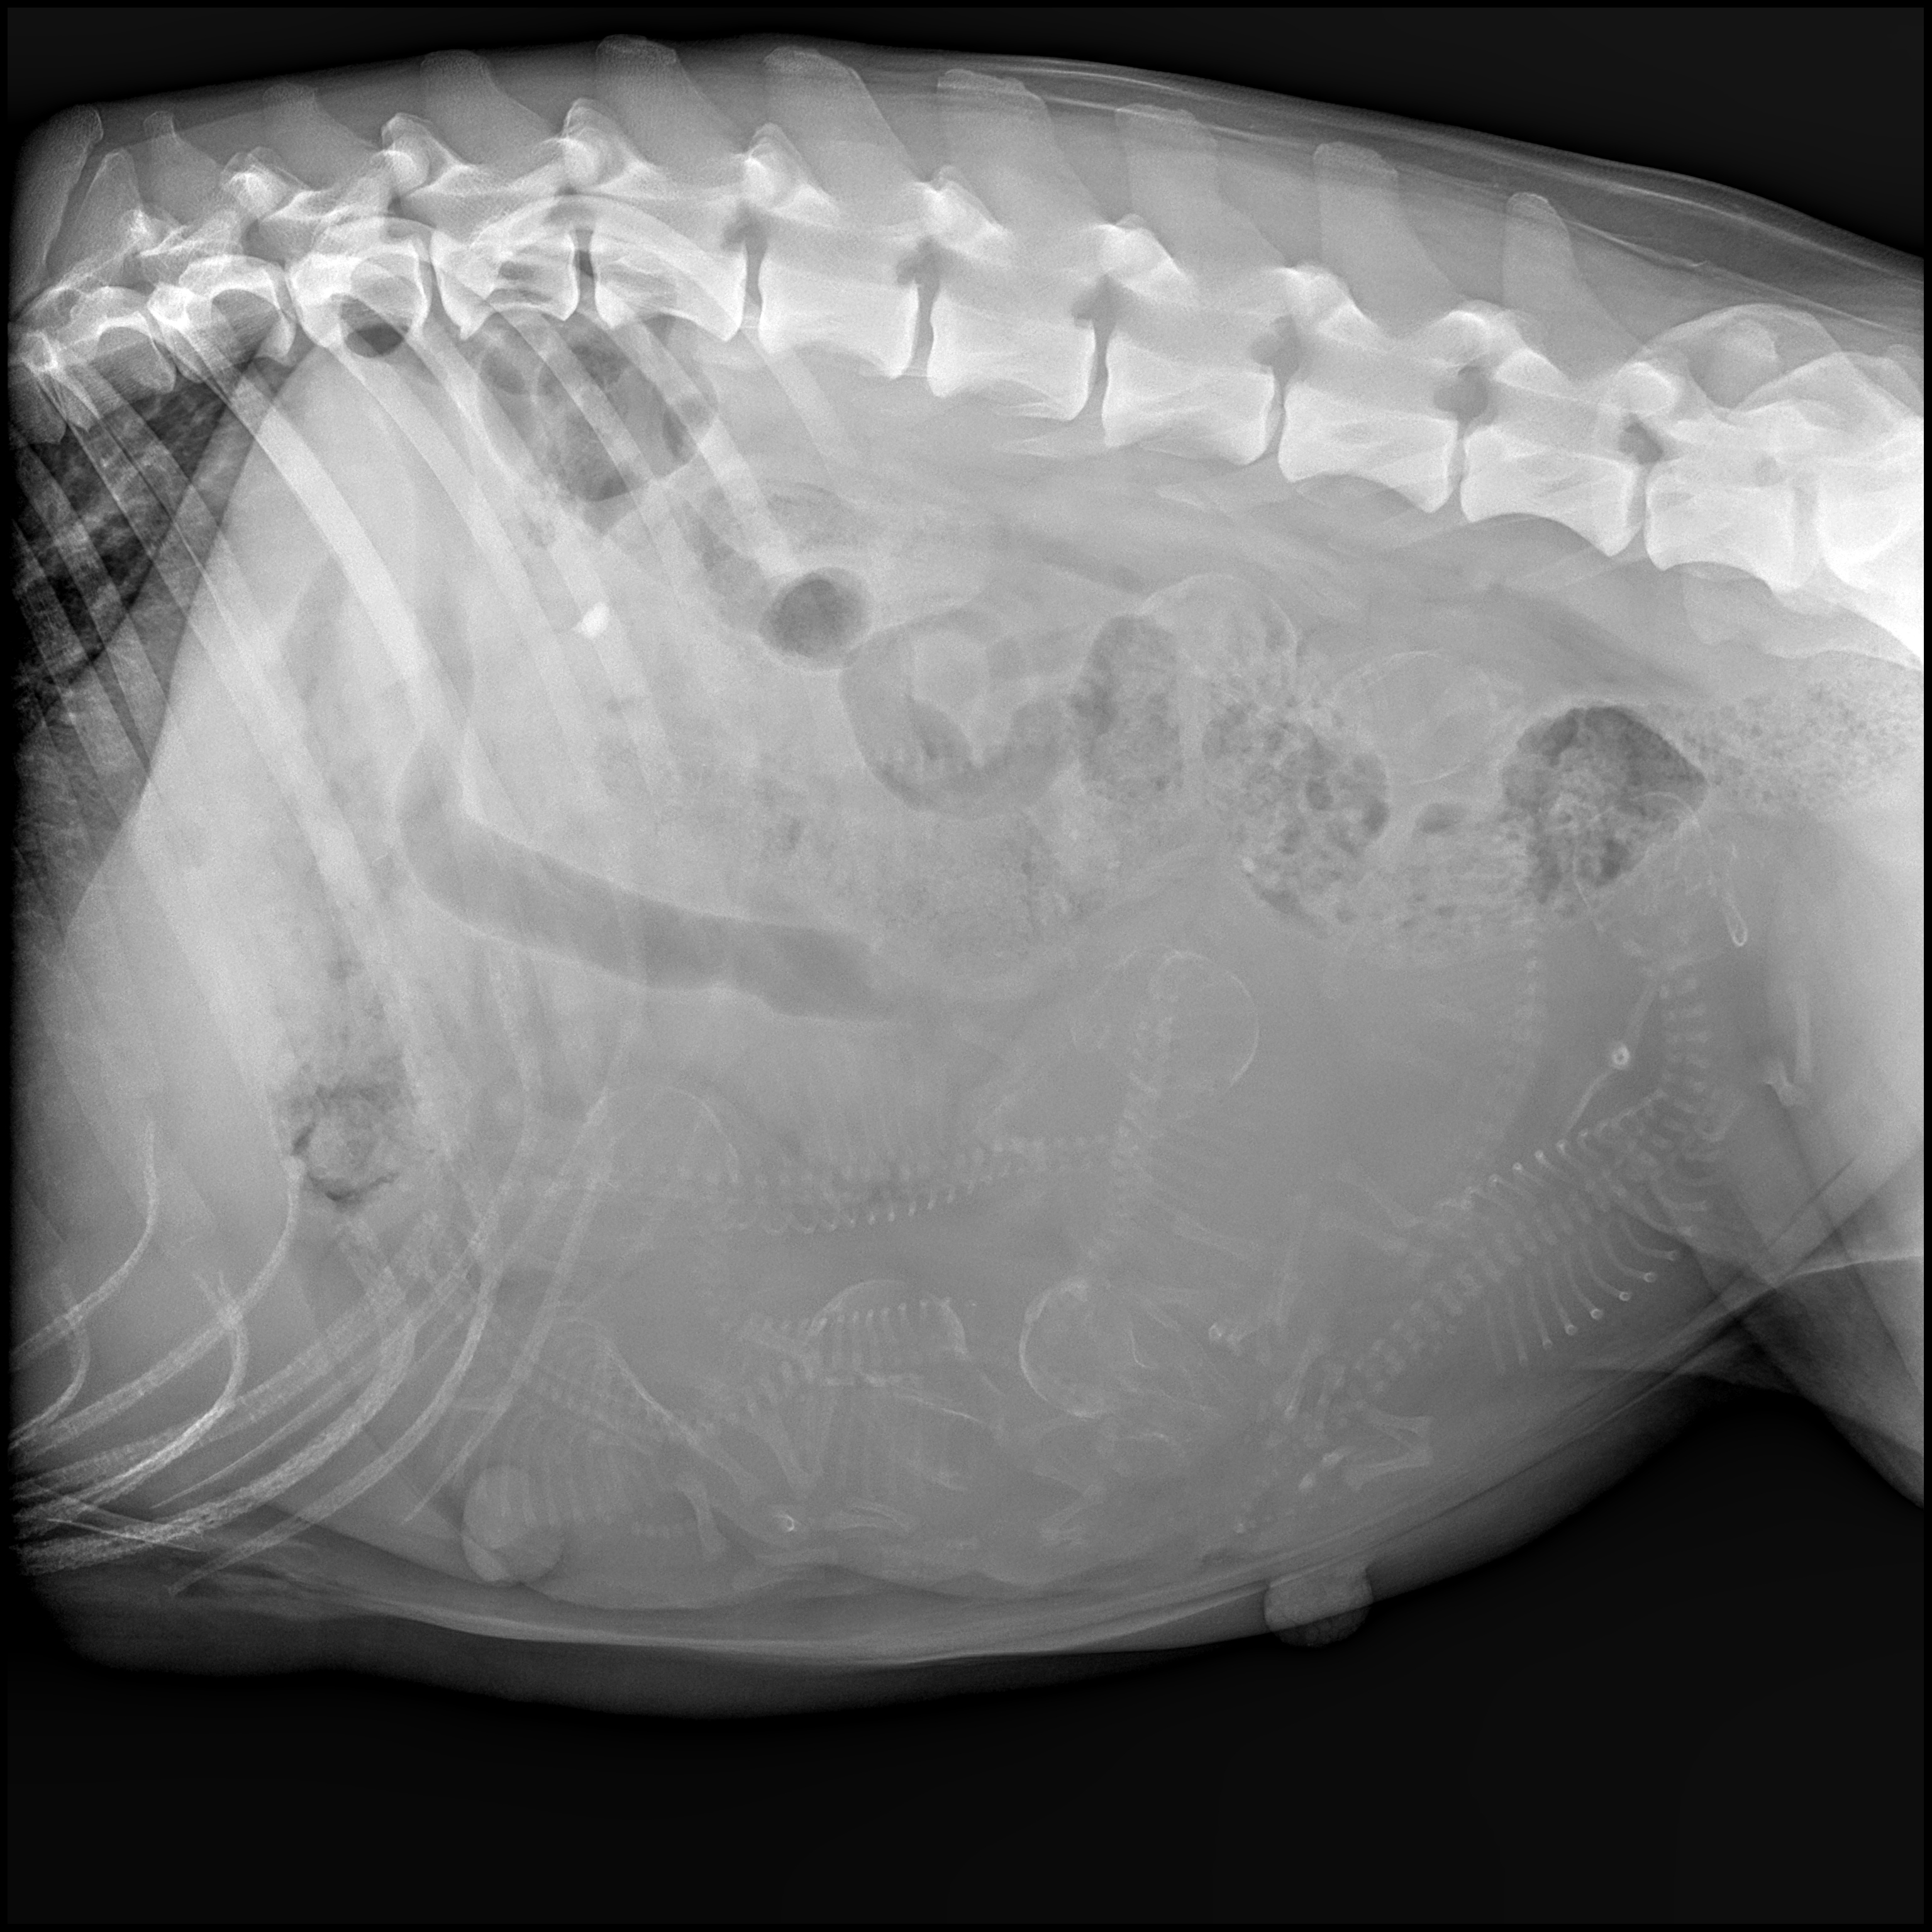

| wir waren beim röntgen und der Tierarzt hat 7 Welpen gezählt. Jetzt heißt es mal wieder abwarten. |